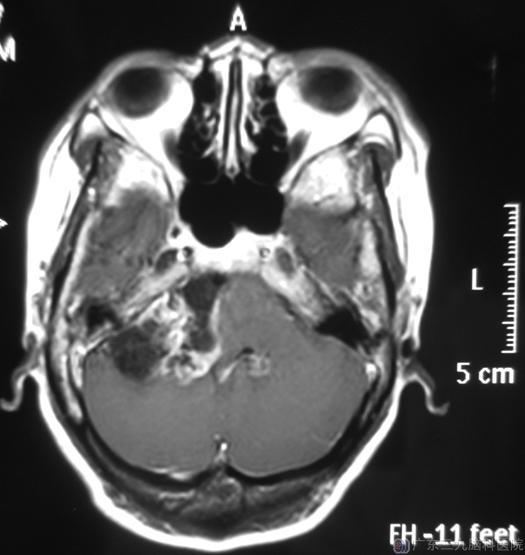

黎姐,两个月前逐渐出现耳鸣,右侧听力明显下降等症状。三天前突然出现头痛,伴间断性头晕,当地医院头部核磁共振检查:右侧桥小脑角占位,考虑听神经瘤,大小约3.5cm×4cm×4.7cm。

手术前